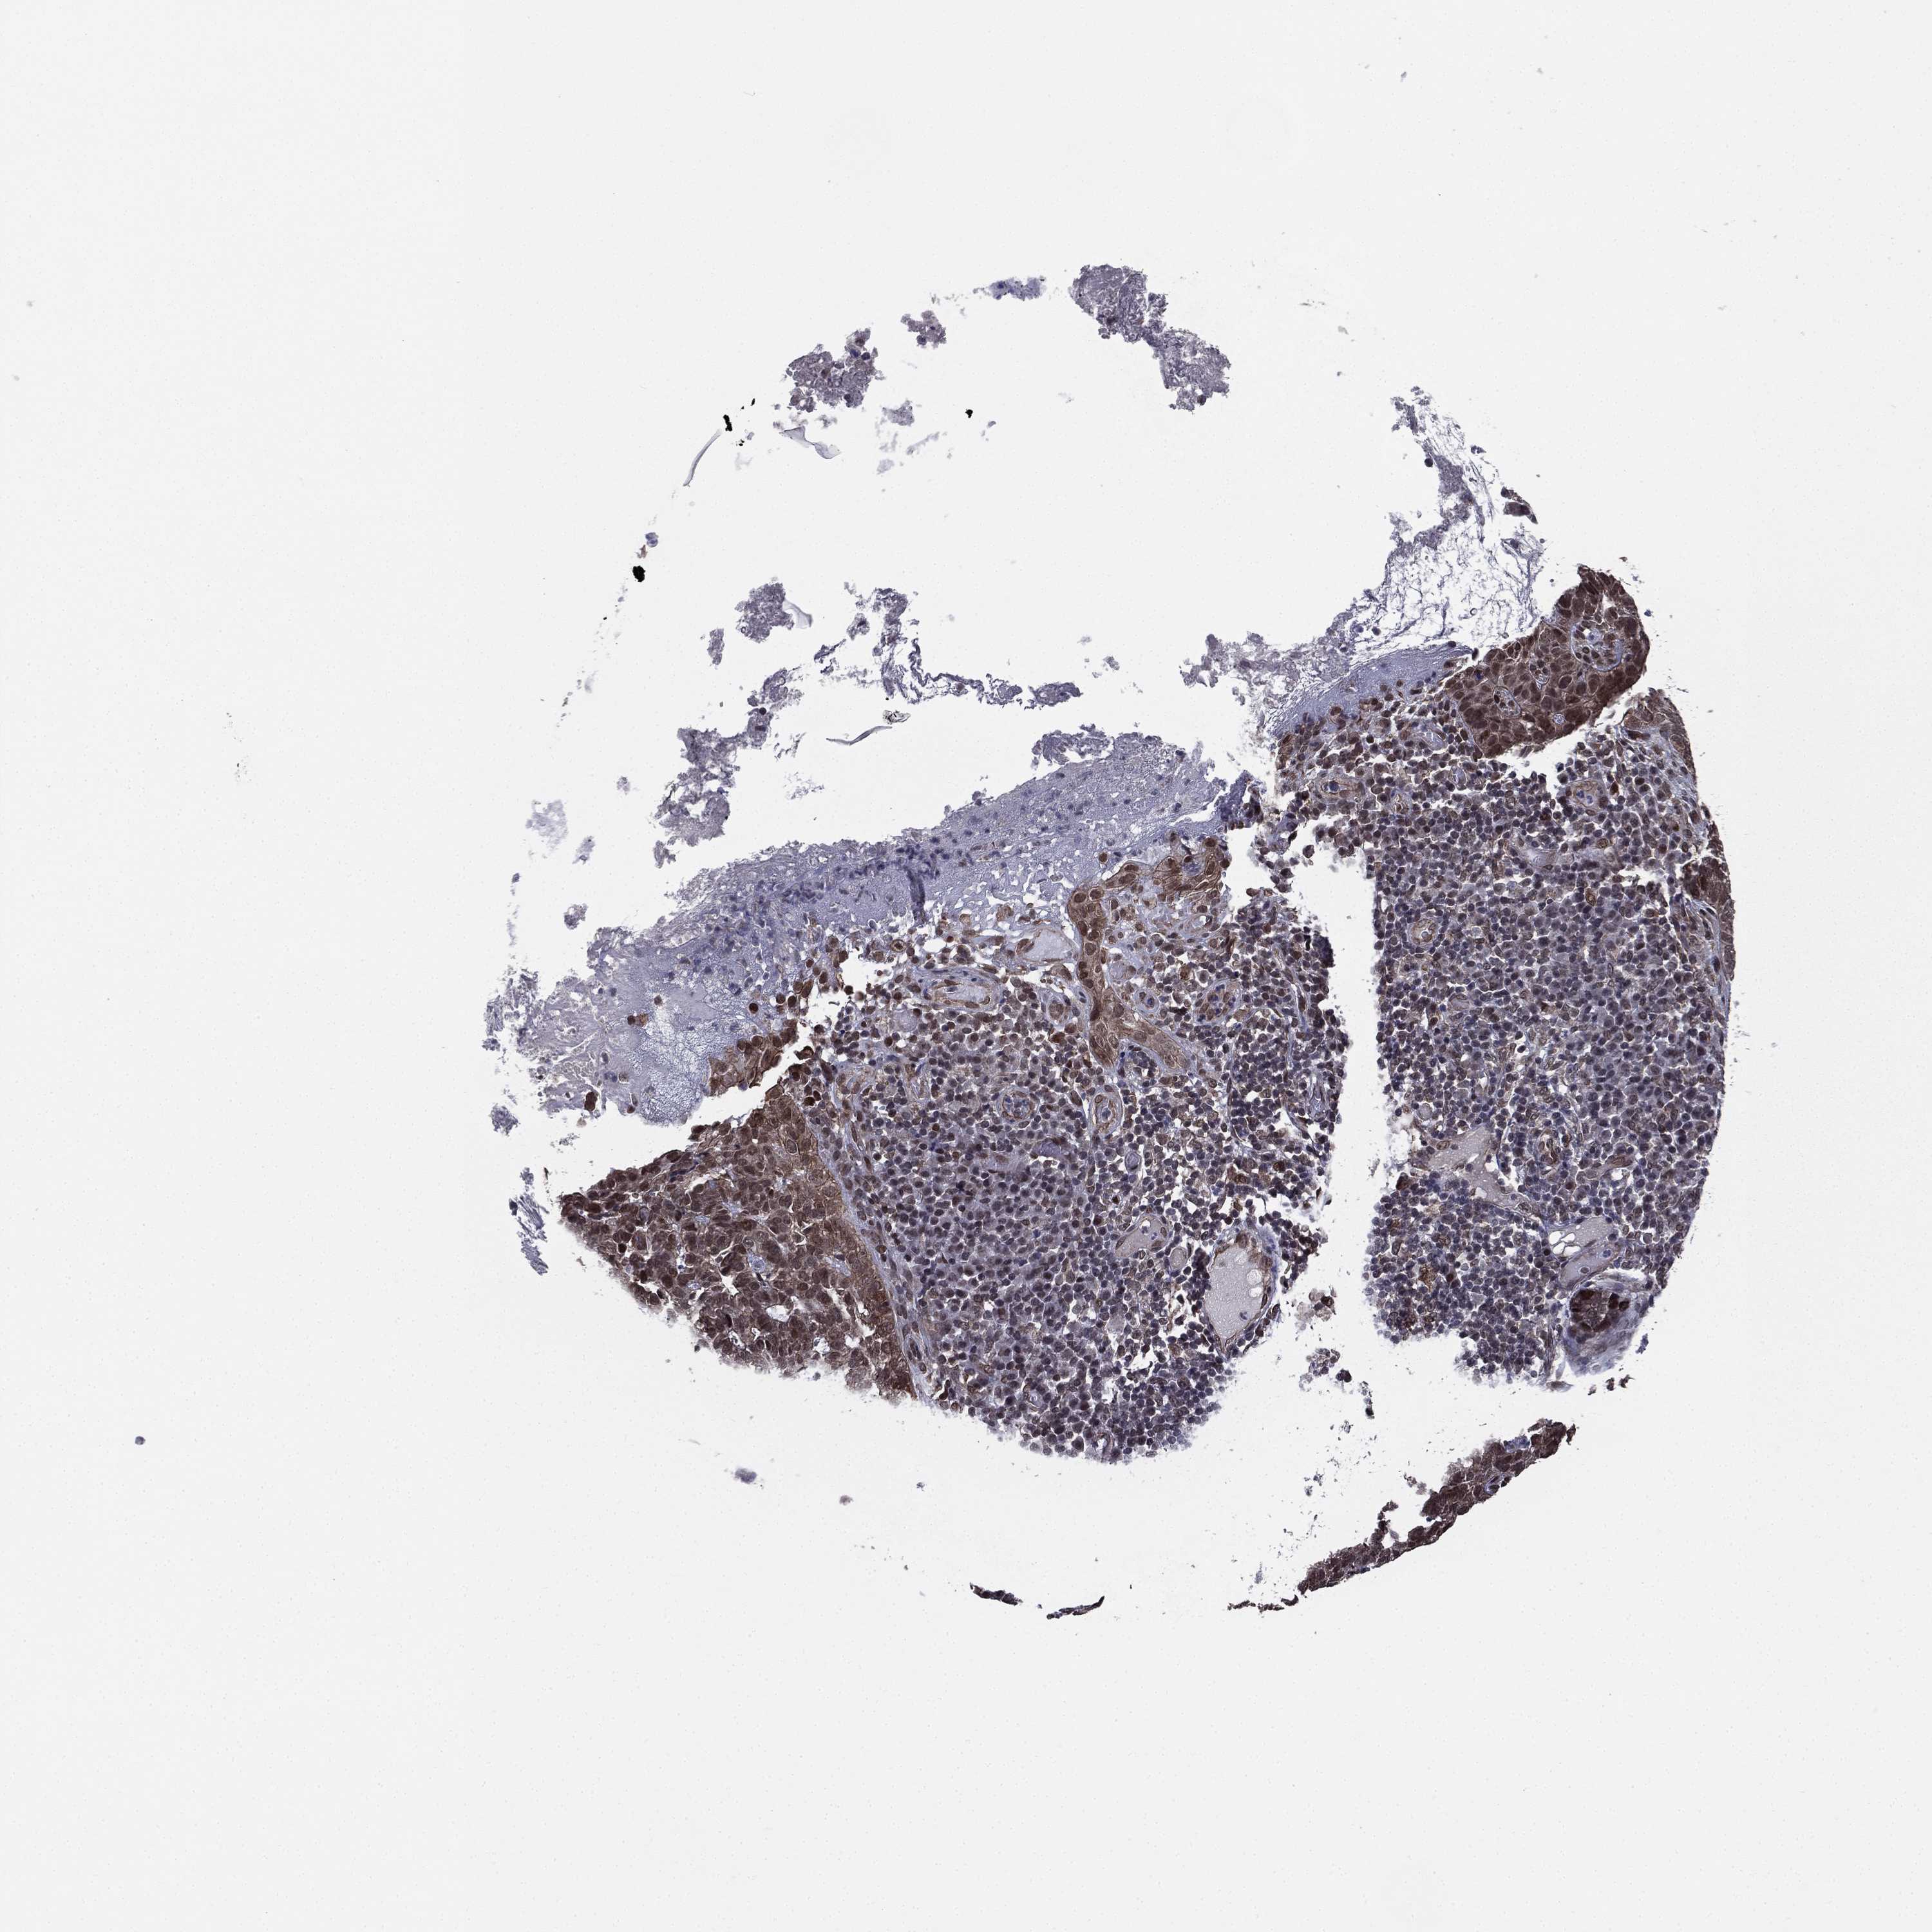

SKIN CANCER - Protein expressioni

A mouse-over function shows sample information and annotation data. Click on an image to view it in a full screen mode. Samples can be filtered based on level of antibody staining by selecting one or several of the following categories: high, medium, low and not detected. The assay and annotation is described here.

Antibody stainingi

Antibody staining in the annotated cell types in the current human tissue is reported as not detected, low, medium, or high, based on conventional immunohistochemistry profiling in selected tissues. This score is based on the combination of the staining intensity and fraction of stained cells.

Each image is clickable and will lead to virtual microscopy that enables deeper exploration of all samples and also displays staining intensity scores, fraction scores and subcellular localization as well as patient and tissue information for each sample.

Antibody HPA004174

Antibody CAB002617

Staining

High

Medium

Low

Not detected

Intensity

Strong

Moderate

Weak

Negative

Quantity

>75%

75%-25%

<25%

None

Location

Nuclear

Cytoplasmic/membranous

Cytoplasmic/membranous,nuclear

Basal cell carcinoma

Squamous cell carcinoma, NOS